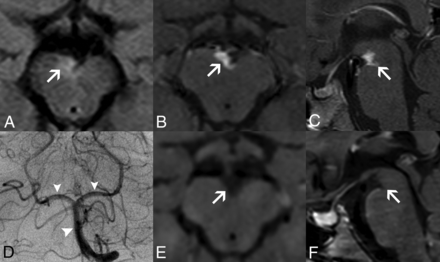

Intracranial hemorrhagic manifestations in adenosine deaminase 2 deficiency. Axial gradient-echo T2-weighted images of patient 4 at 5.8 years of age (A) and patient 11 at 18.3 years of age (B) demonstrate microbleeds in the right lenticular nucleus (arrow) and in the interpeduncular cistern or vessel wall (arrow), respectively. Axial gradient-echo T2-weighted image (C) of patient 1 at 6.1 years of age reveals an acute left temporal hematoma (thick arrow) and a left paramedian occipital microbleed (arrow). None of the patients presented with head CT calcifications in the corresponding locations of the microbleeds (not shown). Axial SWI of patient 5 (D) at 16.5 years of age depicts a right frontoparietal hemorrhagic chronic lesion (thick arrows) causing ex vacuo dilation of the lateral ventricle (asterisks).

The first novel finding in this series was the detection of small parenchymal foci of susceptibility effect in 2 patients with DADA2, likely corresponding to brain microhemorrhages. The latter have been shown to correlate with hemosiderin-laden perivascular macrophages and have been associated with progressive aging and multiple neurologic conditions, including small-vessel disease and CNS vasculitis.19 Another patient presented a similar focal susceptibility effect located in the interpeduncular fossa, likely in a vessel wall, that could have the same origin, considering the absence of intracranial aneurysms and subarachnoid hemorrhage.